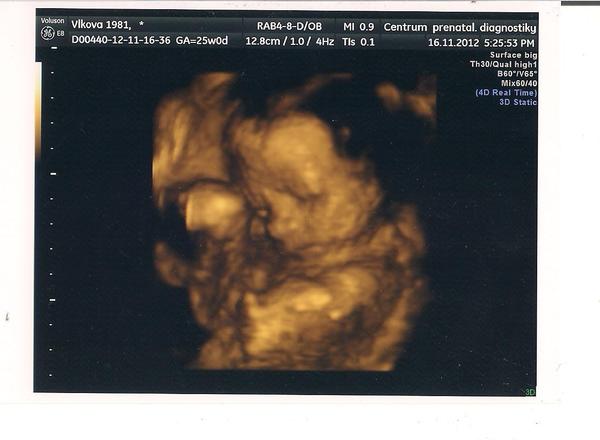

@lenajsek neboj roste,my jsme byli stále v těch nižších velikostech a ted to dohnal ,na 3D Uz v 26.tý jsme měli 880g a pani doktorka říkala,že jsme to pěkně dohnali.

jinak to je náš budulínek a doufám,že se brzo budete z těchto zážitků těšit všechny,držíme palečky